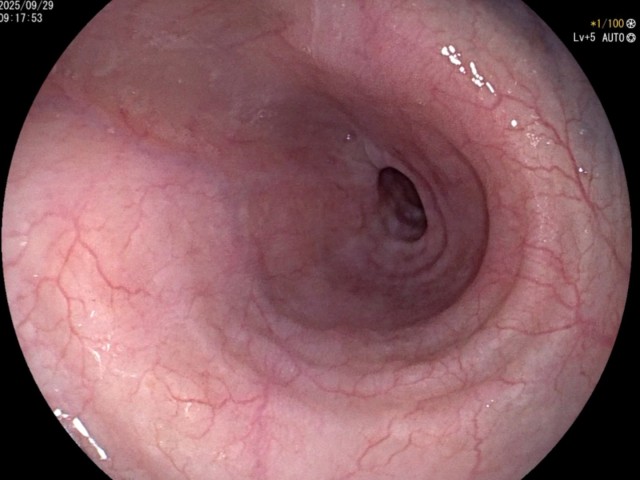

反思 | 赶高铁时一过性晕厥的老年男性

昨天值班遇到的一例晕厥病例,差点漏诊,而最终的解法,始于最简单而质朴的查体。国庆中秋双节的最后一天,8号的早上8点,抢救室床旁晨交班,病人依旧是多而重,交到6床,一个刚入室不久的病人,准备去做CT,夜班医师汇报病史:69岁男性,本次因“头晕伴一过性晕厥1小时”为主诉入抢,1小时前于高铁站因即将赶不上高铁走路快时突发头晕,伴一过性晕厥,约3-4分钟后清醒,清醒后诉今晨未吃早餐,已服用降压药物,仍有头晕头痛、四肢乏力等不适,无胸闷胸痛,无畏寒发热,无咳嗽咳痰,无恶心呕吐,无肢体麻木,无视物模糊等不适,路人拨打120送至我院急诊就诊。既往高血压,长期服用氨氯地平+福辛普利,血压控制一般;糖尿病,长期